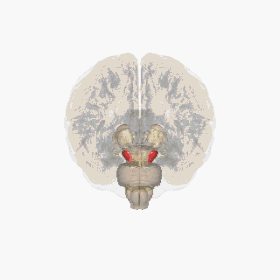

![]() المادة السوداء مُبرَزة باللون الأحمر. | |